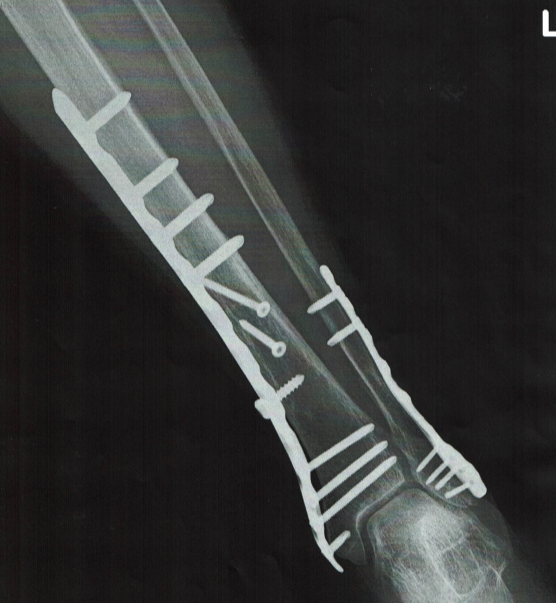

74歳女性 下腿粉砕骨折後の経過

上図に示すように、レントゲン撮影では骨が正常に戻り、回復しました。津美の問題は、この金属を取り除くことの必要性で相談されました。

1. 全身麻酔でのリスク。

2. ボルト17本を抜いた後の穴から亀裂骨折のリスク。

3. 金具を抜く際の皮神経損傷からシビレが消失しない リスク。

4. ボルト、金具が骨と癒着している場合に、神経、筋 への損傷の可能性が否定できないリスク。

74歳女性 下腿粉砕骨折

ヨーロッパ旅行の最終日、湖岸にて写真を撮ろうとした際に足元を滑らせて転倒。地元で手術施行して1週間後に帰国。そのまま総合病院にて受診。

術後10日で抜糸、4週間後にシーネ固定除去。両松葉にて3点支持での歩行練習開始。

当院に歩行練習など相談を受け、往診を継続し、1か月で日常生活動作を指導、治癒。

ボルト除去手術について総合病院の医師から問われ、私は手術の必要性についてご相談を受けました。

私の回答はやめた方が良いという結論です。

1.ボルトが癒着してなかなか除去できない。

2.抜いたボルトの処理をしても、そこから再骨折の可

能性はある。

3.日常生活に問題が無ければ、現状維持で良い。

現在80歳で症状良好を維持しています。